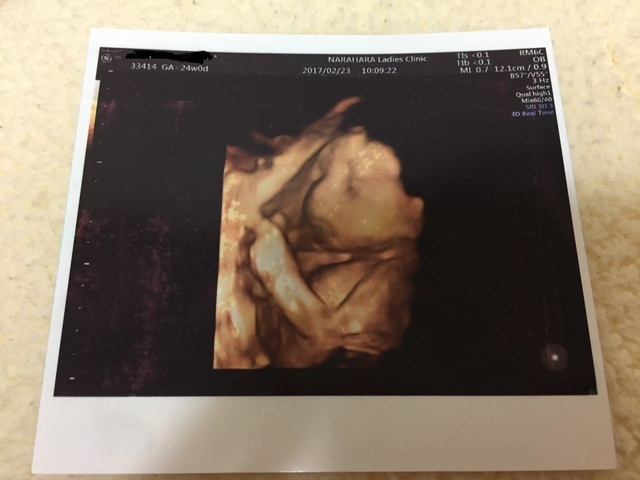

24週0日(24w0d・男の子)|りら# さん(27歳)

エコー写真撮影時のエピソード:

いつも手で隠してなかなか顔を見せてくれなかったけどやっと見せてくれた時のエコー写真。

はっきりと顔立ちが分かって感動したしかわいいと思い、改めてお腹に赤ちゃんがいるという実感が湧いた。過去に死産したことがあるので顔が見れてとても安心した。